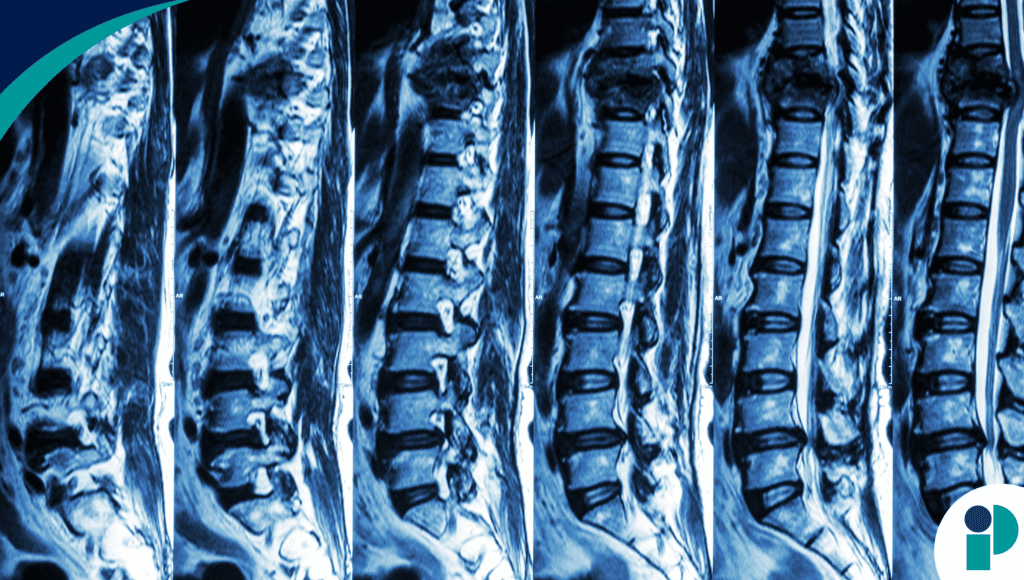

La intervención, prevista para los próximos meses, consiste en implantar un tejido de médula espinal desarrollado en laboratorio a partir de células madre. El objetivo es restaurar las conexiones nerviosas dañadas y permitir que los pacientes con lesiones medulares graves puedan recuperar movilidad y sensibilidad. Los especialistas explicaron que esta técnica va más allá de la reparación física, ya que abre la puerta a futuros tratamientos para enfermedades neurológicas degenerativas como la esclerosis lateral amiotrófica o el Parkinson.

Hasta ahora, los tratamientos disponibles para las lesiones de médula espinal se han limitado a la rehabilitación intensiva, cirugías de estabilización y terapias experimentales que no han logrado resultados concluyentes. Por eso, la noticia ha despertado enorme expectación internacional, ya que por primera vez se plantea una solución real, innovadora y con base científica que podría devolver funciones motoras perdidas.